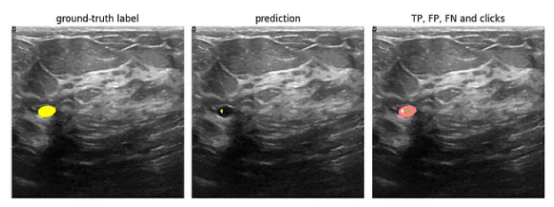

假阴性(图像来源:乳腺超声图像数据集)

注意到,图像左侧似乎有一个感兴趣的区域(RoI)——一个小的、深色的椭圆形。这在标签中显示为黄色区域。但模型的预测是空集——预测帧中没有黄色像素。模型似乎不相信这张照片中有RoI。我们,在这里扮演人类专家的角色,显然是不同意此结果的。